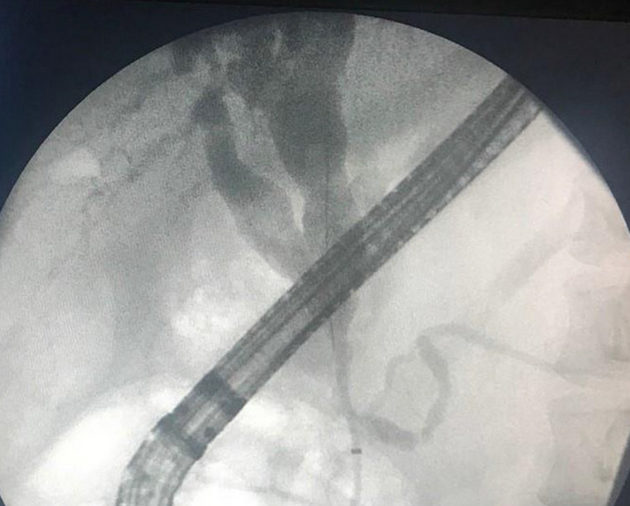

ERCP image of gallbladder stricture. ( Courtesy Dr . V . Penopoulos ) (Courtesy Dr. V. Penopoulos).